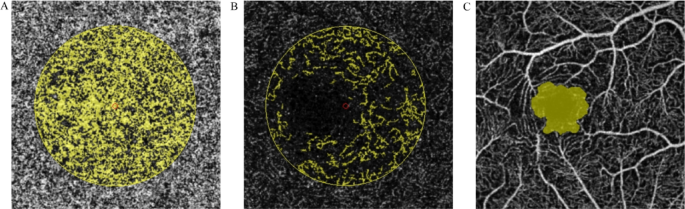

A total of 85 eyes from 64 non-carriers of ApoE ε4 and 29 eyes from 20 ApoE ε4 carriers were included in the study, with the specific selection process illustrated in Fig. 1. Females represented a higher proportion of participants, but no significant difference was observed between the groups (64.1% in non-carriers vs. 65.0% in carriers). Similarly, there were no significant differences in age or educational level between the two groups. Demographic data for the subjects are summarized in Table 1. (Fig. 2).

30 × 30° OCTA images of the central perfusion area at three different levels from a 58-year-old ApoE ε4 carrier. (A) Foveal blood flow area based on choroidal capillaries, the small red circle is the fovea, and the yellow part indicates the area of blood perfusion; (B) Foveal blood flow area based on the outer retina, the small red circle is the fovea, and the yellow part indicates the area of blood perfusion; (C) No central perfusion area based on superficial vascular complex, the yellow part shows the area without blood perfusion.

Figure 2 illustrates eye blood perfusion in a 58-year-old woman. In the FAZ index, the FAZ area (mm2) was significantly lower in ApoE ε4 carriers compared to controls; a trend toward group differences was observed in PERIM (mm) (p = 0.05). No statistically significant differences were found between the groups in AI and FD (%) (Fig. 3).